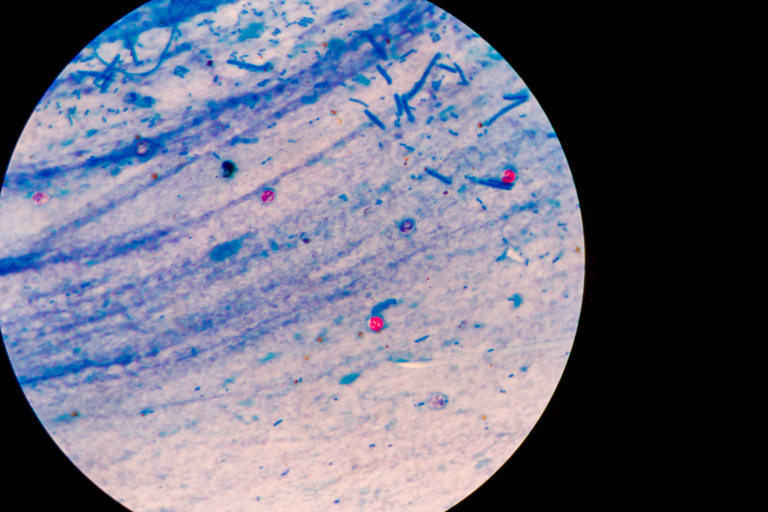

Такъв пример е паразитът Cryptosporidium, който притежава устойчива обвивка и преживява най-дълго в хлорираната вода. Заразяването с него става при поглъщане на вода от басейн, замърсен с паразита, където той може да попадне при къпане на болен човек.

Cryptosporidium е на първо място сред причинителите на инфекции в плувните басейни, следван от бактериите Pseudomonas, Shigella и Legionella.